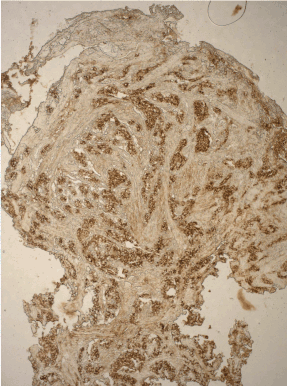

Figure 2. Autoimmune A gastritis: marked G-cell hyperplasia in antral mucosa. ABC x 300.